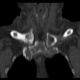

Женщина за 50 лет. Жалобы на припухлость и болезненость в области правого грудинно-ключичного сочленения. Принял решение не проводить рентгенографию, а сразу направить на КТ.

Хорошо. Тогда - мнение врача КТ, с коим я абсолютно согласен, - асептический некроз грудинного конца ключицы.

Не против того, что в какой то мере здесь присутствуют и явления артрозо-артрита, но ТАКИЕ изменения структуры грудинного конца ключицы, да еще и с наличием секвестров, вряд ли были бы характерны только для артроза.

1.Клинически при осмотре - припухлость, болезненная, без особых наружных признаков воспаления, существующая несколько месяцев, медленно прогрессирующая в размерах, ограничение движения в плече (из за болезненности в ключично-грудинном сочленении).

Не вижу явных признаков некроза, а вот изменения суставной поверхности в виде изьеденности по ключице и грудине пристутствуют. Единственное минус - нет расширения суставной щели. То, что принимаете за секвестры, скорее всего, являются изменениями края кости за счёт воспаления окружающих тканей: ревматоидный артрит (к примеру). В таких случаях проверяю себя УЗИ (изменения мягких тканей).

1. Если бы не вовлечённость значительной части ключицы (кости), тоже бы заключил артрозо-артрит.

2. Я не врач КТ, но. имея некоторый рентгенологический и клинический опыт прихожу к выводу. что сия ситуация выходит за рамки артрозо-артрита, а первое мнение было именно врача КТ - об асептическом некрозе.

4. Меня, в первую очередь, смущает тоже большой обьем поражения кости, что не характерно для артроза.

Вижу подобную картину не так уж и редко и трактую это как артроз-артрит. Причем, вижу это в ста процентах случаев как случайную находку (пациенты с ДТП и прочие травматики) и без всякой клиники в анамнезе. Убедительных данных (признаков) за ас.некроз тут не вижу. У меня нет наработок, какие изменения происходят в итоге в костях суставов при зазличных видах артритов. Вероятно, что разница может быть очень серьезная.

Ладно, предположим. Асептический некроз. Но сейчас-то мы видим явную дегенератику + склеротическое уплотнение + клиника. Чем не банальные артрозоартритные дела с морфологической декомпенсацией? Или мы говорим об исходе асептического некроза?